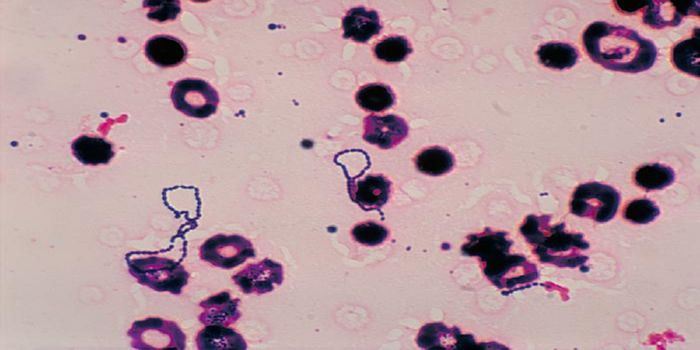

FEB 21, 2016Clinical & Molecular DXA staggering 30-50% of the world’s population is estimated to be infected with the parasite Toxoplasma gondii. Thi ...